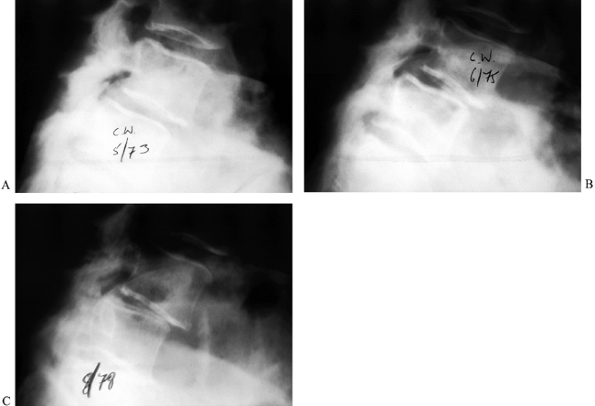

the amount of vertebral subluxation; often, they also reveal a pars

interarticularis defect if one is present (Fig. 162.4). Oblique views have also been used to highlight the Scotty-dog sign (Fig. 162.5). In young patients, flexion–extension

lying in the lateral decubitus position rather than standing (60). Plain standing radiographs are also quite useful for documenting progression of deformity (Fig. 162.6).

Figure 162.5. Varied radiographic appearance of spondylolysis without olisthesis. A: Oblique radiograph shows lysis at L-3. Note the collar on Scotty dog. B: Oblique radiograph reveals atrophic nonunion at an L-5 pars defect. Oblique (Scotty dog) radiographs reveal a pars defect (C) and an elongated healed pars (D)

in the same patient with a low-grade slip. (Courtesy of Harry Griffiths, MD, University of Missouri Health Sciences Center, Columbia, MO.) |

![]() |

|

Figure 162.6. Progression of degenerative spondylolisthesis at L4-5 over a 5-year period as seen on lateral radiographs. A: 1973. B: 1975. C: 1978. (Courtesy of Harry Griffiths, MD, University of Missouri Health Sciences Center, Columbia, MO.)